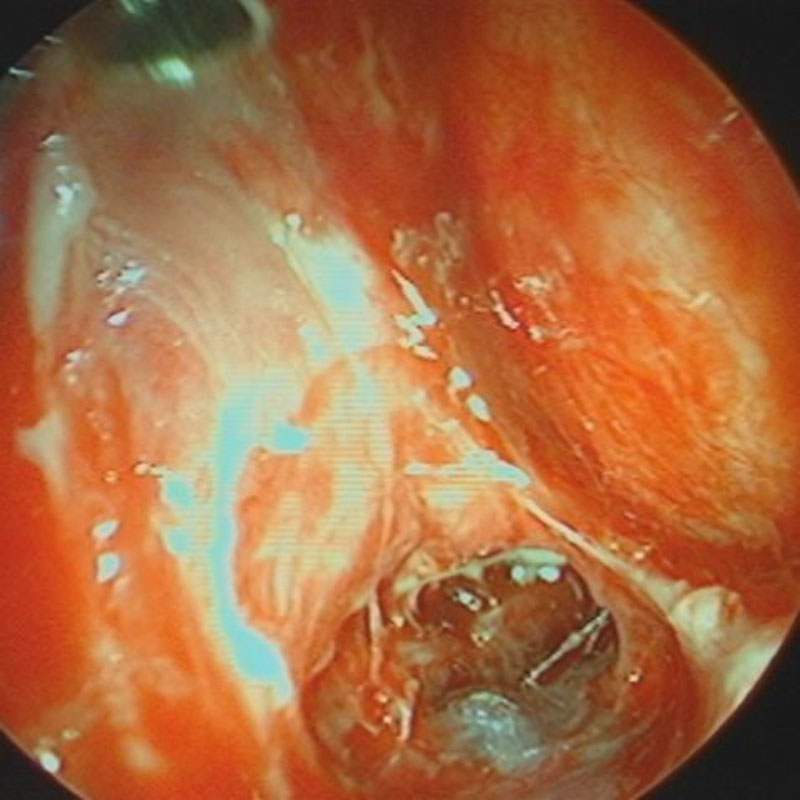

412

'23年5月

20代

小脳血管芽腫

頭蓋内腫瘍摘出術

No.’23_46 手術前1

No.’23_46 手術前2

No.’23_46 摘出 前

No.’23_46  摘出 中

No.’23_46 摘出 後